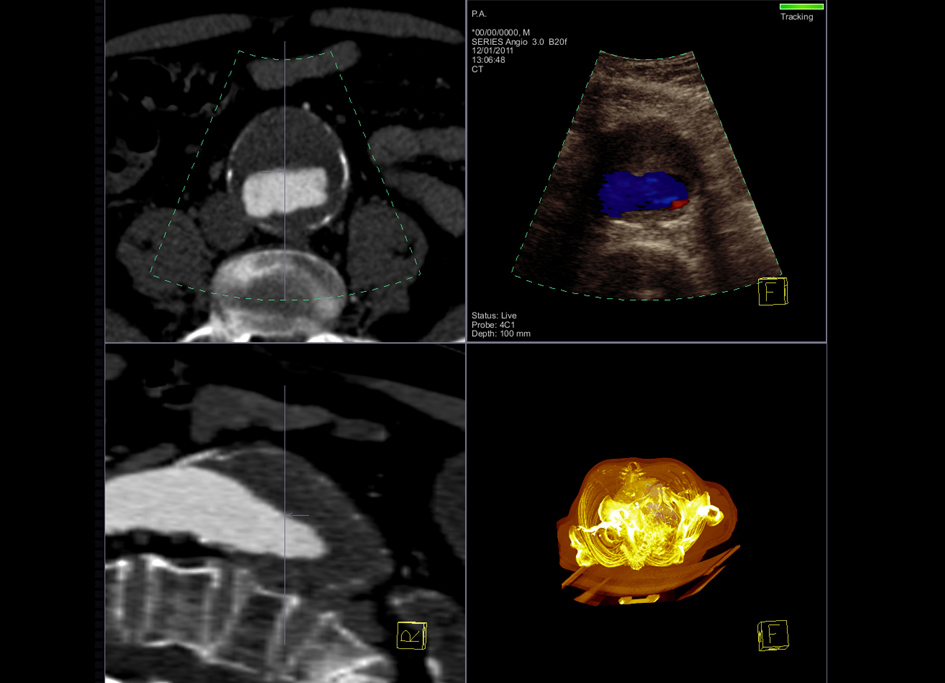

La empresa Siemens ha creado el dispositivo Acuson S3000 con el que se fusiona las imágenes de Tomografía Computarizada o Resonancia Magnética, con las ecografías utilizando el mapa del escáner como patrón para conocer dónde se encuentra la lesión y así hacer la punción a través de eco.

El principal objetivo de los avances en diagnóstico por imagen es obtener una mayor calidad de imagen para poder diagnosticar cada vez con mayor precisión. En este sentido, los numerosos beneficios de la fusión de imágenes de Tomografía Computarizada (TC) o Resonancia Magnética (RM) con ecografía indican que el futuro de la imagen médica pasa por la consolidación de esta técnica. Así se ha puesto de manifiesto en el XXXI Congreso de la Sociedad Española de Radiología Médica (SERAM), que se celebra en Granada.

A menudo, con una técnica primaria como el TC o la RM, es difícil diagnosticar una lesión o una patología de manera exacta. Sin embargo, al sumar imágenes de diferentes técnicas, se obtiene una imagen de mayor calidad y, por tanto, un diagnóstico mucho más fiable. Además de facilitar una decisión más exacta sobre la lesión o la patología, la fusión de imágenes, presenta importantes ventajas en términos de seguridad, confort y ahorro en costes al realizar una biopsia. Cuando se fusionan imágenes de TC con ecografía, se utiliza el mapa del escáner como patrón para conocer dónde se encuentra la lesión y así hacer la punción a través de eco. De este modo, se evita exponer al paciente de nuevo a radiación y se reducen las listas de espera y los altos costes de pruebas como el TC o la Resonancia Magnética.

No obstante, las técnicas de fusión actuales requieren un registro manual de las imágenes de TC o de RM, un proceso que es lento. También se necesita que el paciente esté tumbado e inmóvil durante toda la exploración para evitar las realineaciones manuales. Para salvar estas limitaciones, Siemens Healthcare ha lanzado su última plataforma para ecografía, el equipo Acuson S3000. Este nuevo sistema de ultrasonidos representa un avance importante para este campo, en el que Siemens es pionero con su tecnología patentada eSie Fusion. Este sistema permite la fusión automática de imágenes tomográficas computarizadas (TC) en 3D con la ecografía en tiempo real con un solo click. De este modo, el registro de la imagen de TC se reduce a unos segundos y se simplifican de manera significativa las técnicas de registro manual por lo que se consigue optimizar el flujo de trabajo durante el registro de volumen en la RM.

El doctor Dirk-André Clevert, profesor adjunto y jefe de sección del Centro Interdisciplinario de Ecografías del Hospital Universitario Grosshadern de Múnich (Alemania), y uno de los primeros médicos que probó el sistema eSie Fusion, ha señalado que “la aplicación de la nueva tecnología de adquisición de imágenes eSie Fusion nos permite acelerar significativamente nuestro flujo de trabajo. Previamente, el éxito de las intervenciones se controlaba mediante el seguimiento con TC. No obstante, ante la nueva solución de fusión ecográfica, sería posible reducir el número de seguimientos que deben hacerse con TC. El uso de la fusión nos permite mejorar la información clínica sin aumentar la radiación. Se trata de una gran ventaja, tanto para el paciente como para el profesional sanitario”.